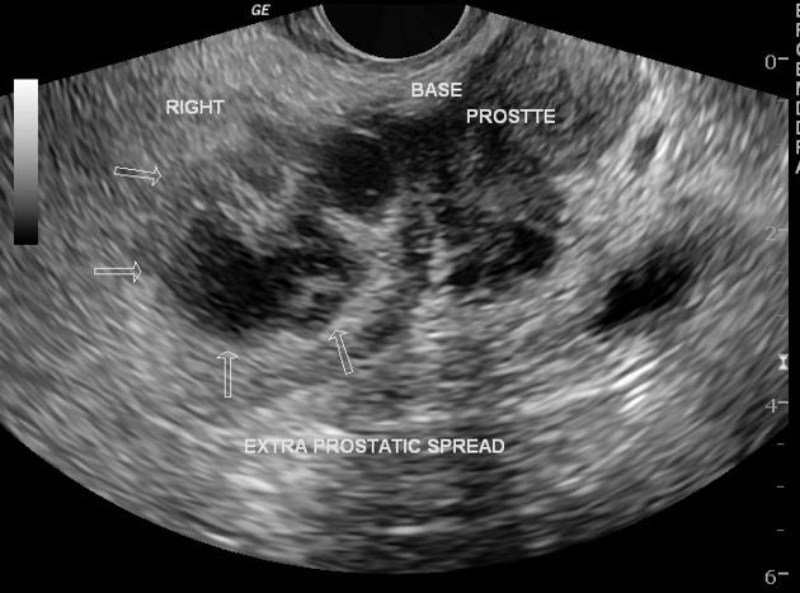

Ung thư tuyến tiền liệt cũng có thể biểu hiện dưới dạng mô tuyến có hồi âm không đồng đều, đặc biệt ở vùng ngoại vi (phần ngoài của tuyến). Sự phát triển ác tính của các tế bào tuyến tiền liệt có thể xuất hiện dưới dạng vùng giảm âm (tối hơn) hoặc đẳng âm (có hồi âm tương tự mô xung quanh), khiến việc nhận diện trở nên khó khăn. (3)

Siêu âm Doppler máu cho thấy lưu lượng máu tăng cũng có thể liên quan đến ung thư tuyến tiền liệt.